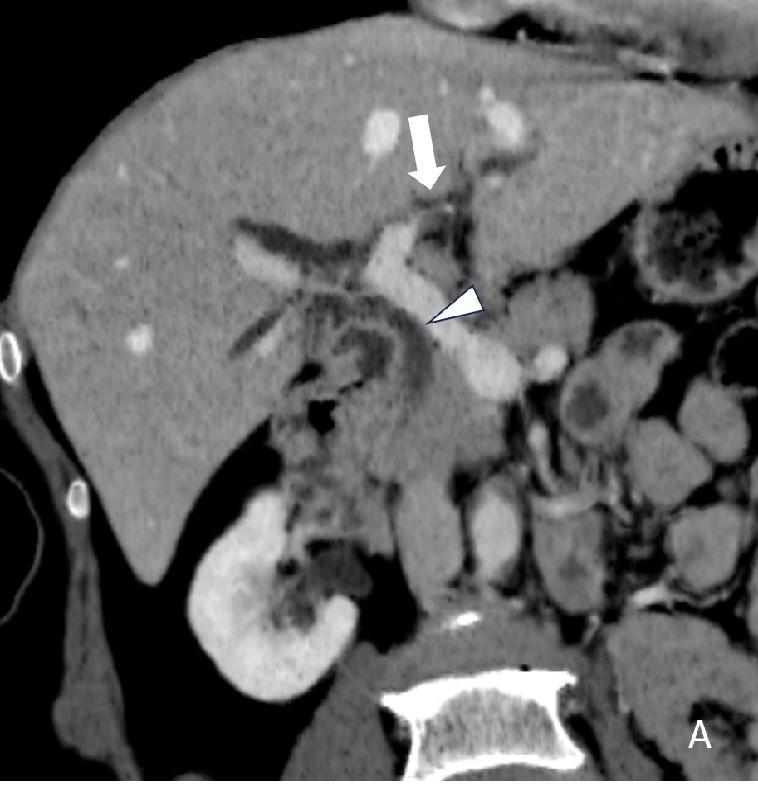

Cholangiocarcinoma (CCA) is an aggressive malignancy with a poor prognosis. Bile duct and peribiliary changes related to CCA may present on ultrasound (US) findings. This study aims to evaluate US findings that could be used as predictors for developing CCA through our surveillance program in an endemic area of Thailand.

The study population was 4,337 villagers in Northern Thailand with a 5-year abdominal US surveillance. Patient demographics data and ultrasound findings of calcifications/granulomas, periductal fibrosis, and diffuse bile duct dilatation were included. A logistic regression model was used to determine significant predictors.

There were 4,225 people included with an average age of 45.49±7.66 years. Prevalence of calcifications/granulomas, periductal fibrosis, and diffuse bile duct dilatation detected on baseline sonographic surveillance was 11.7%, 20.5%, and 11.3%, respectively. The univariate analysis for significant predictors for CCA include age (Relative Risk; RR = 1.12), family history of CCA (RR = 2.29), periductal fibrosis (RR=2.38), and diffuse bile duct dilatation  (RR = 7.59). The multivariate analysis the independent predictors were age (RR = 1.12), family history of CCA (RR = 1.92), and diffuse bile duct dilatation (RR = 5.94), respectively.

The sonographic predictor for CCA surveillance in endemic areas is diffuse bile duct dilatation.  Age and family history of CCA are also helpful clinical markers.